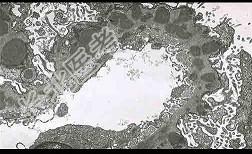

- 单项选择题光镜和电镜肾脏病理表现如下(图-1PAS基底膜增厚,中度系膜增生, 图-2上皮下电子致密物沉积),其符合下面哪种病理类型 ( )

A、膜性肾小球肾炎

B、局灶节段性肾小球硬化

C、膜增生性肾小球肾炎

D、肾小球轻微病变

E、局灶性肾炎